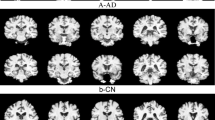

LinkNet3d can effectively achieve skull separation

The Dice coefficient of LinkNet3d is 0.9715, indicating a 97.15% overlap between the predicted mask and the ground truth mask. Intersection over Union (IoU) is a metric used to evaluate the accuracy of an object detector on a particular dataset. In this case, the IoU is 0.9446, indicating that the intersection over union of the predicted and ground truth masks is 94.46%. The separation effect is shown in Fig. 1, where the separated skull region is clear and well-defined, highly consistent with the original image. LinkNet3d optimizes the layer as a heatmap, which, when overlaid with the original image, helps users intuitively understand the model’s focus areas. To enhance computational efficiency, LinkNet3d employs VFM (Variable Feature Map) links between the encoder and decoder blocks, significantly reducing the number of parameters in the network. Compared to the traditional U-Net model, which has 2,673,795 parameters, LinkNet3d has only 2,126,258 parameters, a reduction of ~20.4%. This lightweight design not only lowers memory usage but also accelerates inference speed, making it highly suitable for resource-constrained environments. The model was evaluated on an NVIDIA RTX 3060 GPU with 12GB of VRAM, demonstrating its efficiency and practicality for deployment on mid-range hardware. The main purpose of the LinkNet3d model is to provide high-quality input images for subsequent model training. By effectively separating the skull region, we ensure that downstream models can be trained on cleaner and more accurate images, thereby improving the overall performance and reliability of the diagnostic system.

The first row is the unprocessed image. The second row is the processed image. They all come from different layers of MRI slices of the same person.